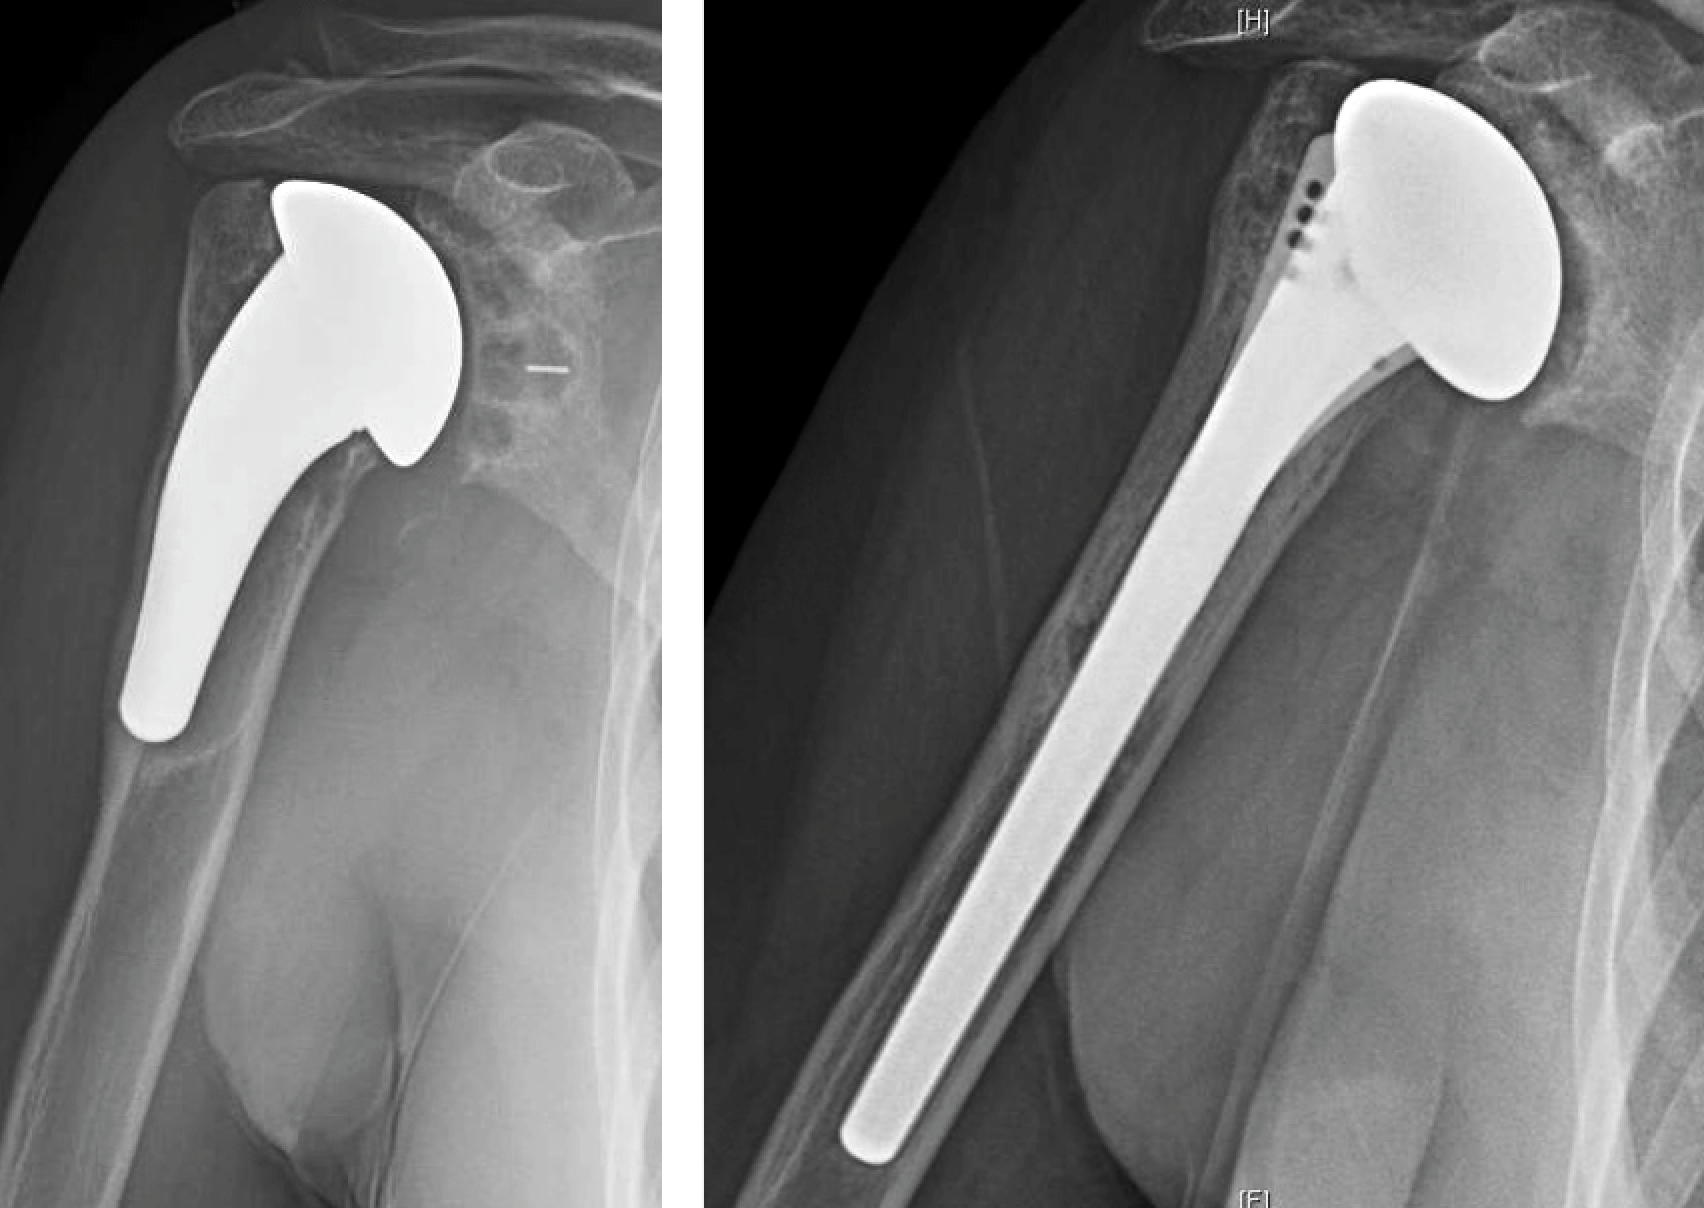

Anatomic Total Shoulder Arthroplasty

What Is Anatomic Shoulder Replacement . Anatomic total shoulder replacement surgery. Anatomic shoulder replacement is indicated for patients with refractory pain in the shoulder due to osteoarthritis. In shoulder replacement surgery, the damaged parts of the shoulder are removed and replaced with artificial components, called a prosthesis. The specific type of shoulder. Total shoulder replacement, also known as total shoulder arthroplasty, is a procedure where portions of the bones in the shoulder joint are removed and replaced with. What is a shoulder replacement? A patient with severe shoulder pain, joint stiffness and grinding may be a candidate for anatomic total shoulder replacement surgery. People with severely damaged rotator cuffs, no rotator cuffs, or shoulder fractures get reverse total shoulder replacement. A shoulder replacement is a procedure that tries to eliminate the source of pain and dysfunction by replacing damaged parts of the shoulder.